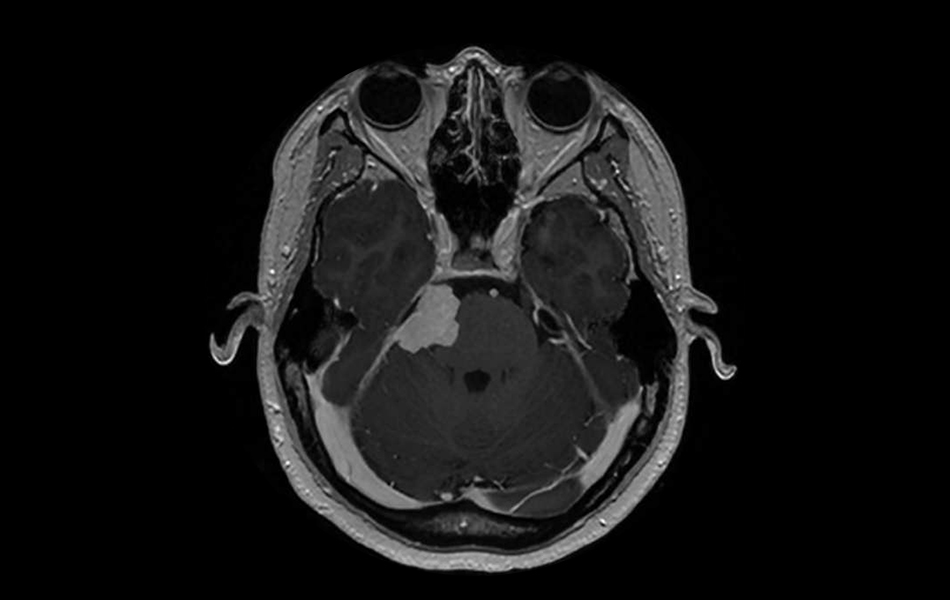

Several recent studies point to an increased risk that women have of developing a meningioma when using injectable birth control. But only a total of about 50,000 people in the U.S. are diagnosed with this type of brain tumor each year.

“While this is certainly the most common brain tumor, brain tumors aren’t all that common to begin with,” said David Raleigh, MD, PhD, a UC San Francisco physician-scientist, director of the UCSF Translational Meningioma Program, and principal investigator at the UCSF Brain Tumor Center. “The absolute risk of developing a meningioma is still very low.” Read article here